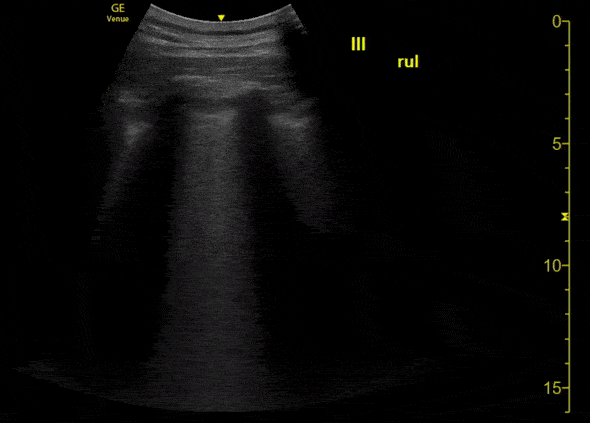

This is an ultrasound clip of the right upper lobe of a patient with confirmed COVID-19 pneumonia. The patient presented to the emergency department on day 3 of symptoms with fever. They were found to be tachypneic and with mild hypoxia. [Clip 1/3] Lung ultrasound demonstrates confluent B lines associated with thickening and irregularity of the pleural line. A thin parapneumonic effusion can also be appreciated here. Image courtesy of Fritz Fuller (@POCUS_Society)